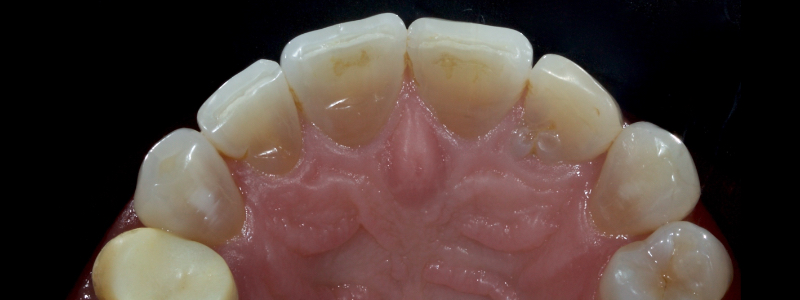

The anterior teeth had lost around 25% of the coronal structure, and dentin was exposed (Figs. 1–3). The patient requested a minimally invasive solution.

After deprogramming with a splint and occlusal equilibration, the anterior teeth were restored with direct composite resin using a minimal prep approach (Figs. 4 and 5). The occlusal scheme was idealized (Fig. 6).